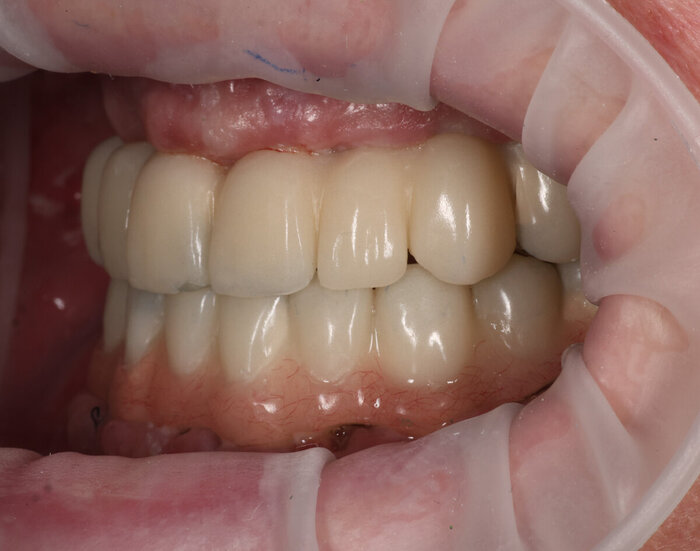

Временный адаптационный протез с опорой на 6 имплантов.

Временный адаптационный протез с опорой на 6 имплантов

Временный адаптационный протез с опорой на 6 имплантов. Нижняя челюсть.